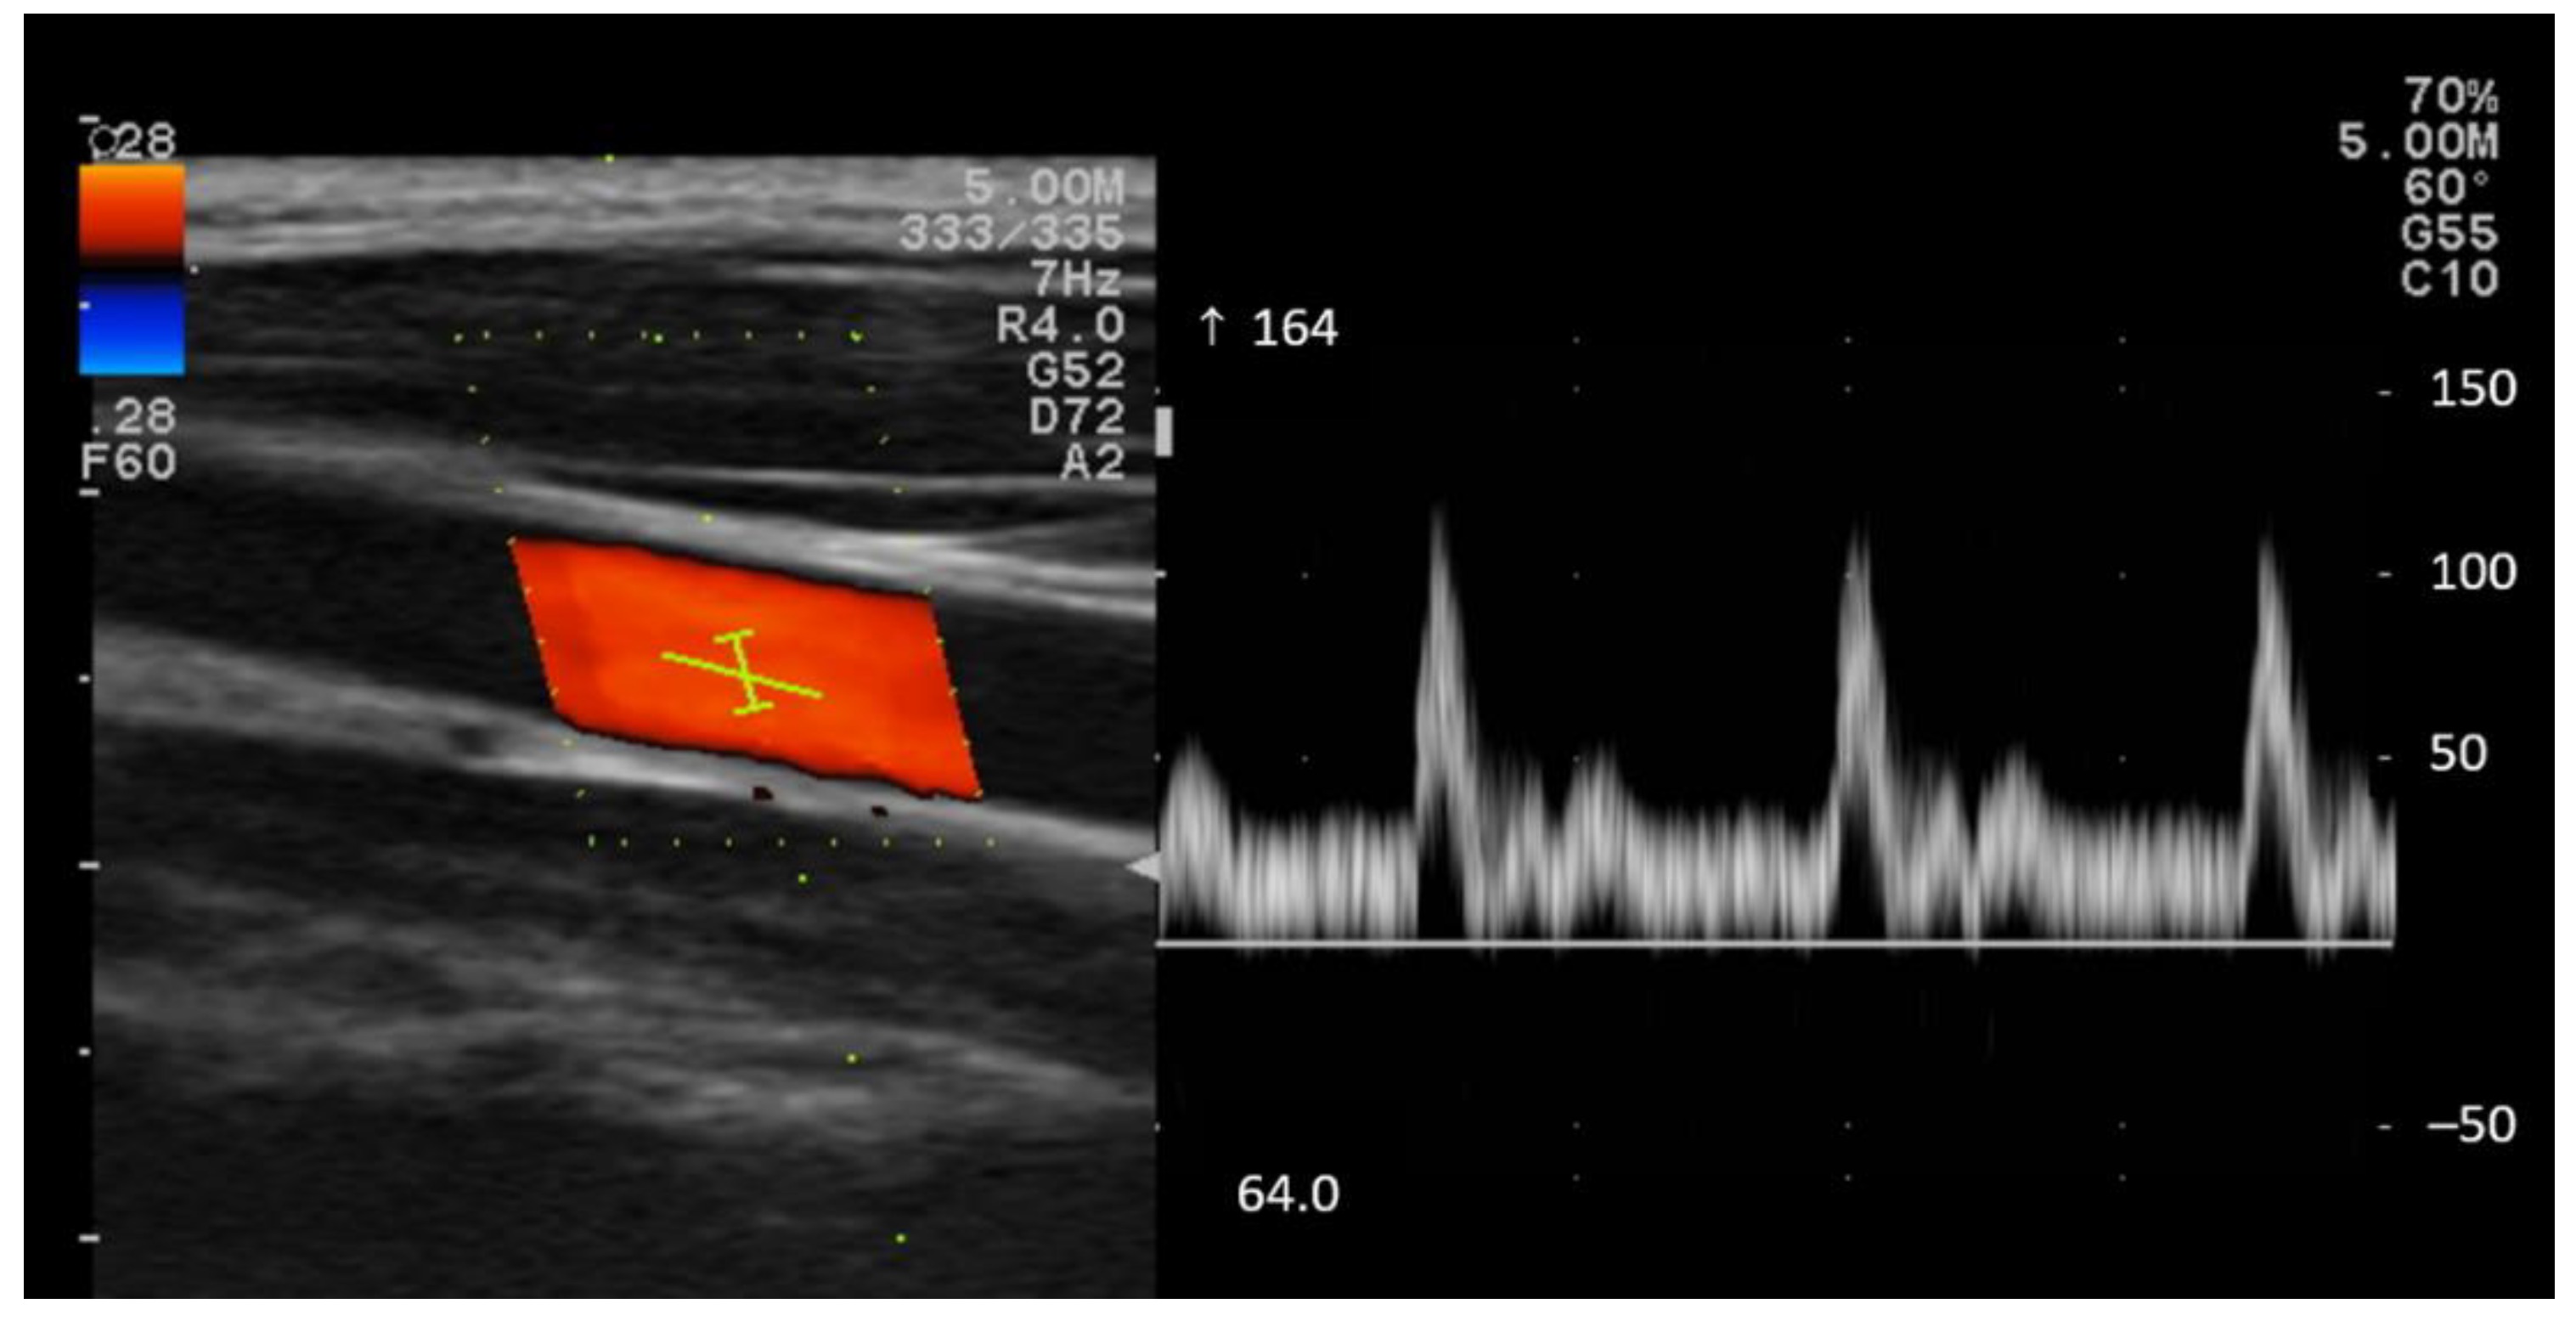

2.4.4. Blood Velocity

3.2.3. Blood Velocity of CCA

4.4. Blood Velocity